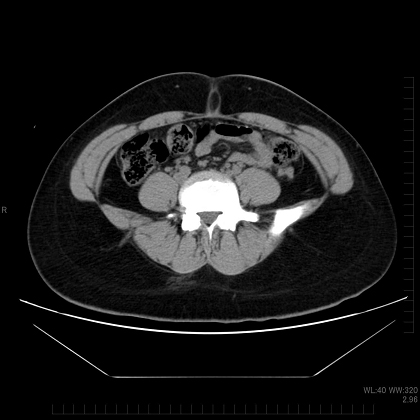

体脂肪には、皮下脂肪と内臓脂肪の2種類があります。指でつまめるのが皮下脂肪、体の奥に隠れているのが内臓脂肪で、それぞれのタイプを皮下脂肪型肥満、内臓脂肪型肥満と呼びます。

内臓脂肪は、わりと最近になってから存在が確認されました。CTスキャンが実用化し、体を輪切りにした画像が容易に得られるようになったからです。こうして画像で見ると、違いは一目瞭然ですね。

一般的には、内臓脂肪はつきやすく取れやすい、皮下脂肪はつきにくいが取れにくいという傾向があります。

内臓脂肪型肥満